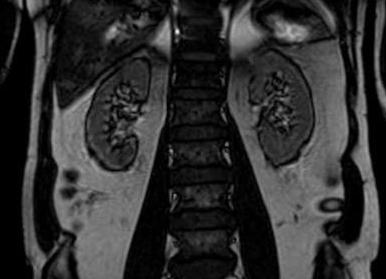

Снимки, полученные в ходе исследования

Что показывает процедура?

Магниторезонансная томография выявляет следующие заболевания:

- Аномальные характеристики развития органов мочевыводящей системы.

- Различного рода воспаления с прогрессирующим инфицированием путей и протоков системы.

- Наличие туберкулеза почек и всей мочевыводящей системы.

- Некроз тканей органа, неправильное кроветворение.

- Последствия травм и операций в области мочеточников, почек и других близлежащих органов.

- Нарушения в состоянии сосудов почечной системы.

- Гидронефроз.

- Присутствие паразитов в почках и признаки их поражения.

- Возможные опухоли.

В перечень не входит диагностика мочекаменной болезни, так как в данном случае МРТ обладает низкой информативностью. Для выявления посторонних объектов в органе необходимо, чтобы они содержали жидкость. Камни являются безжидкостной консистенцией, поэтому для их изучения подойдут такие способы, как компьютерная томография (КТ) и рентген-обследование.